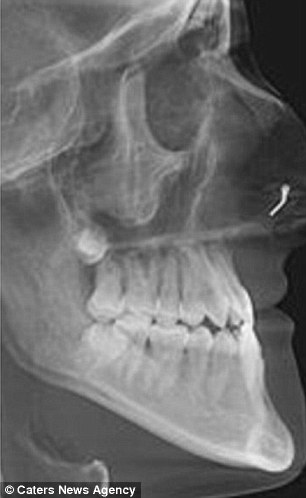

Se le recomendó que se operara a la edad de 12 años para lidiar con la clase tres de la mordida y la mandíbula subdesarrollada. Pero, después de retrasar el tratamiento, su condición empeoró en tres años.

Para reparar la deformidad, a Lauren se le rompieron las dos mandíbulas y luego se volvieron a juntar usando 36 tornillos y hueso insertado en su barbilla. No solo la cirugía redujo el tamaño del mentón, ahora Lauren puede respirar adecuadamente y su ceceo ha desaparecido por completo.